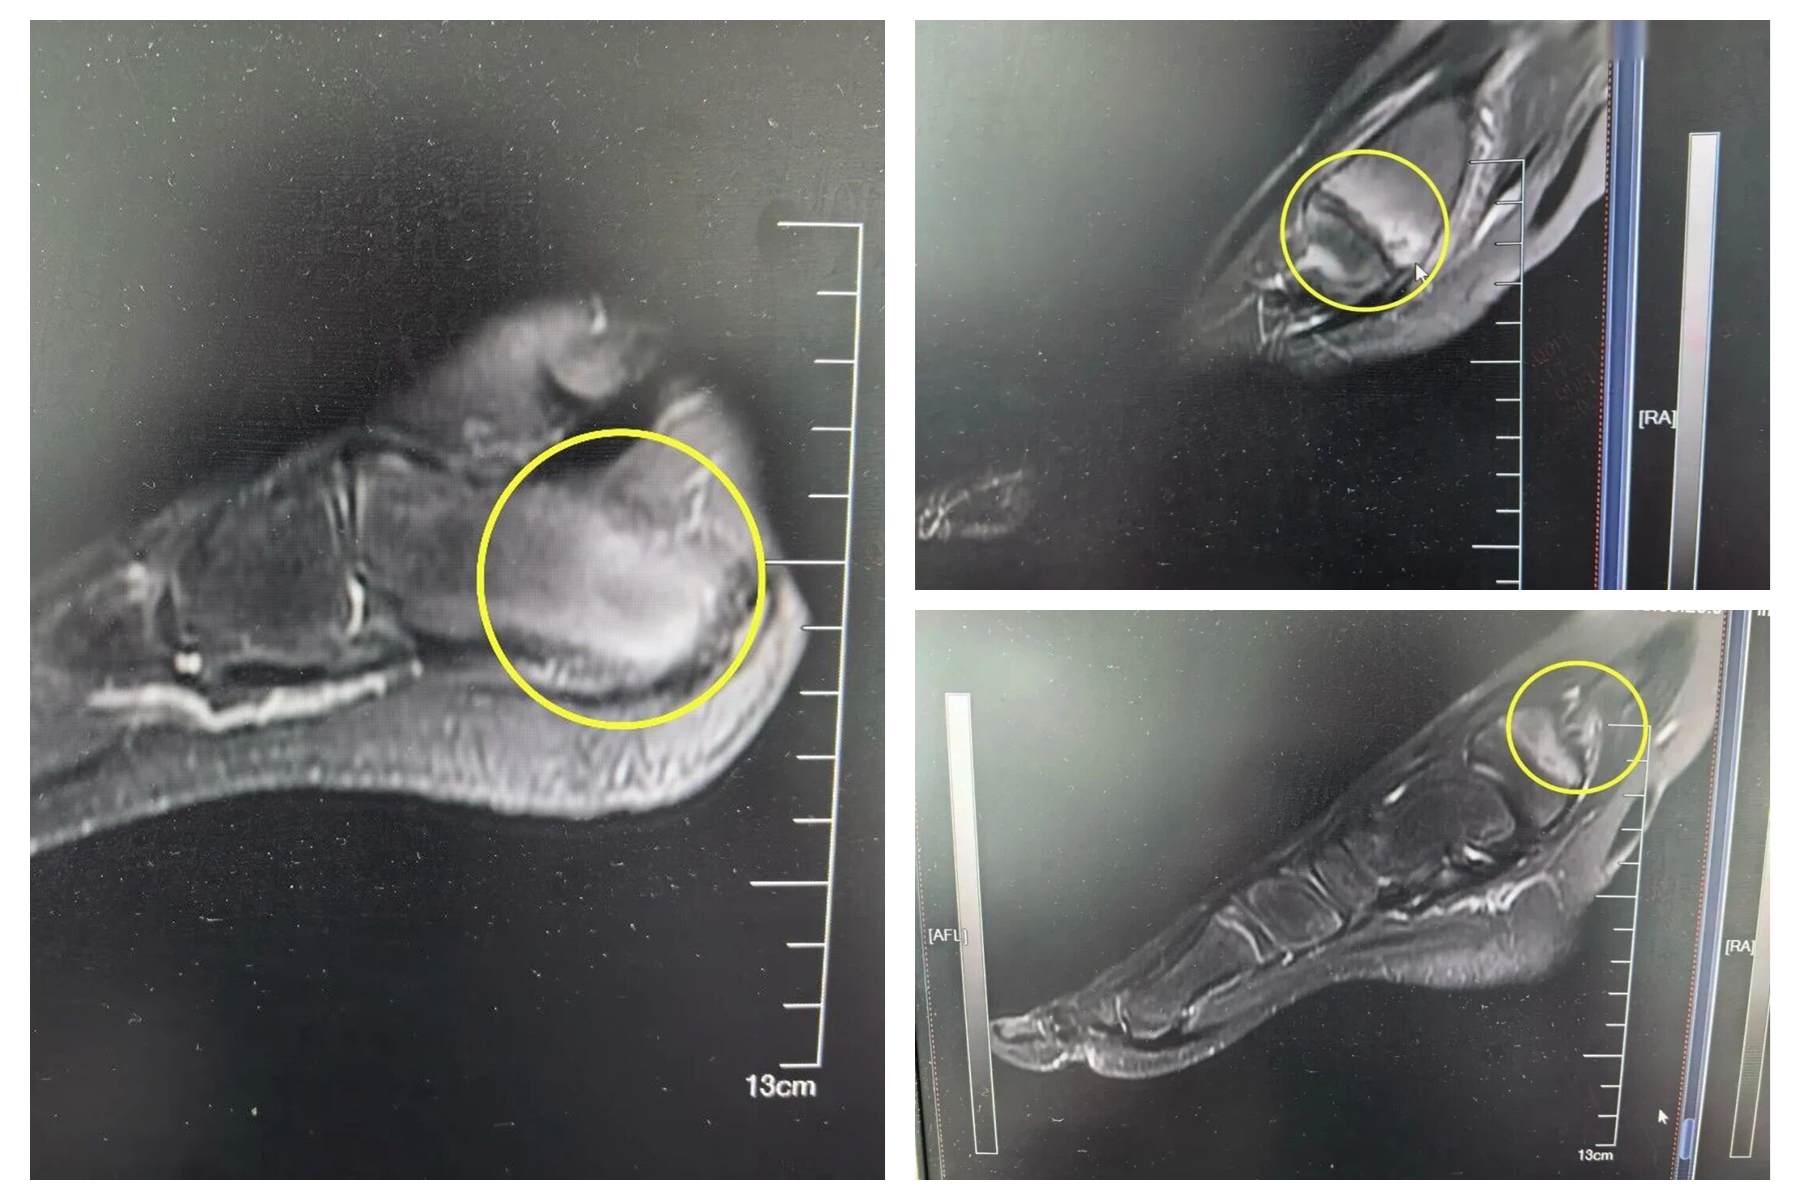

皮皮踝关节的损伤,并非单纯关节炎表现,而是先出现长骨损害,再逐步累及关节面,这一特征并不符合普通关节炎或外伤性关节损伤的表现,而是指向骨源性病变。

顺着这一思路,进一步完善关节影像学检查,结果显示皮皮存在多发骨质破坏、骨髓水肿,同时炎症指标升高,而类风湿因子、HLA-B27等阴性,排除肿瘤、感染性、自身免疫疾病依据,经综合分析,最终确诊为慢性复发性多灶性骨髓炎。